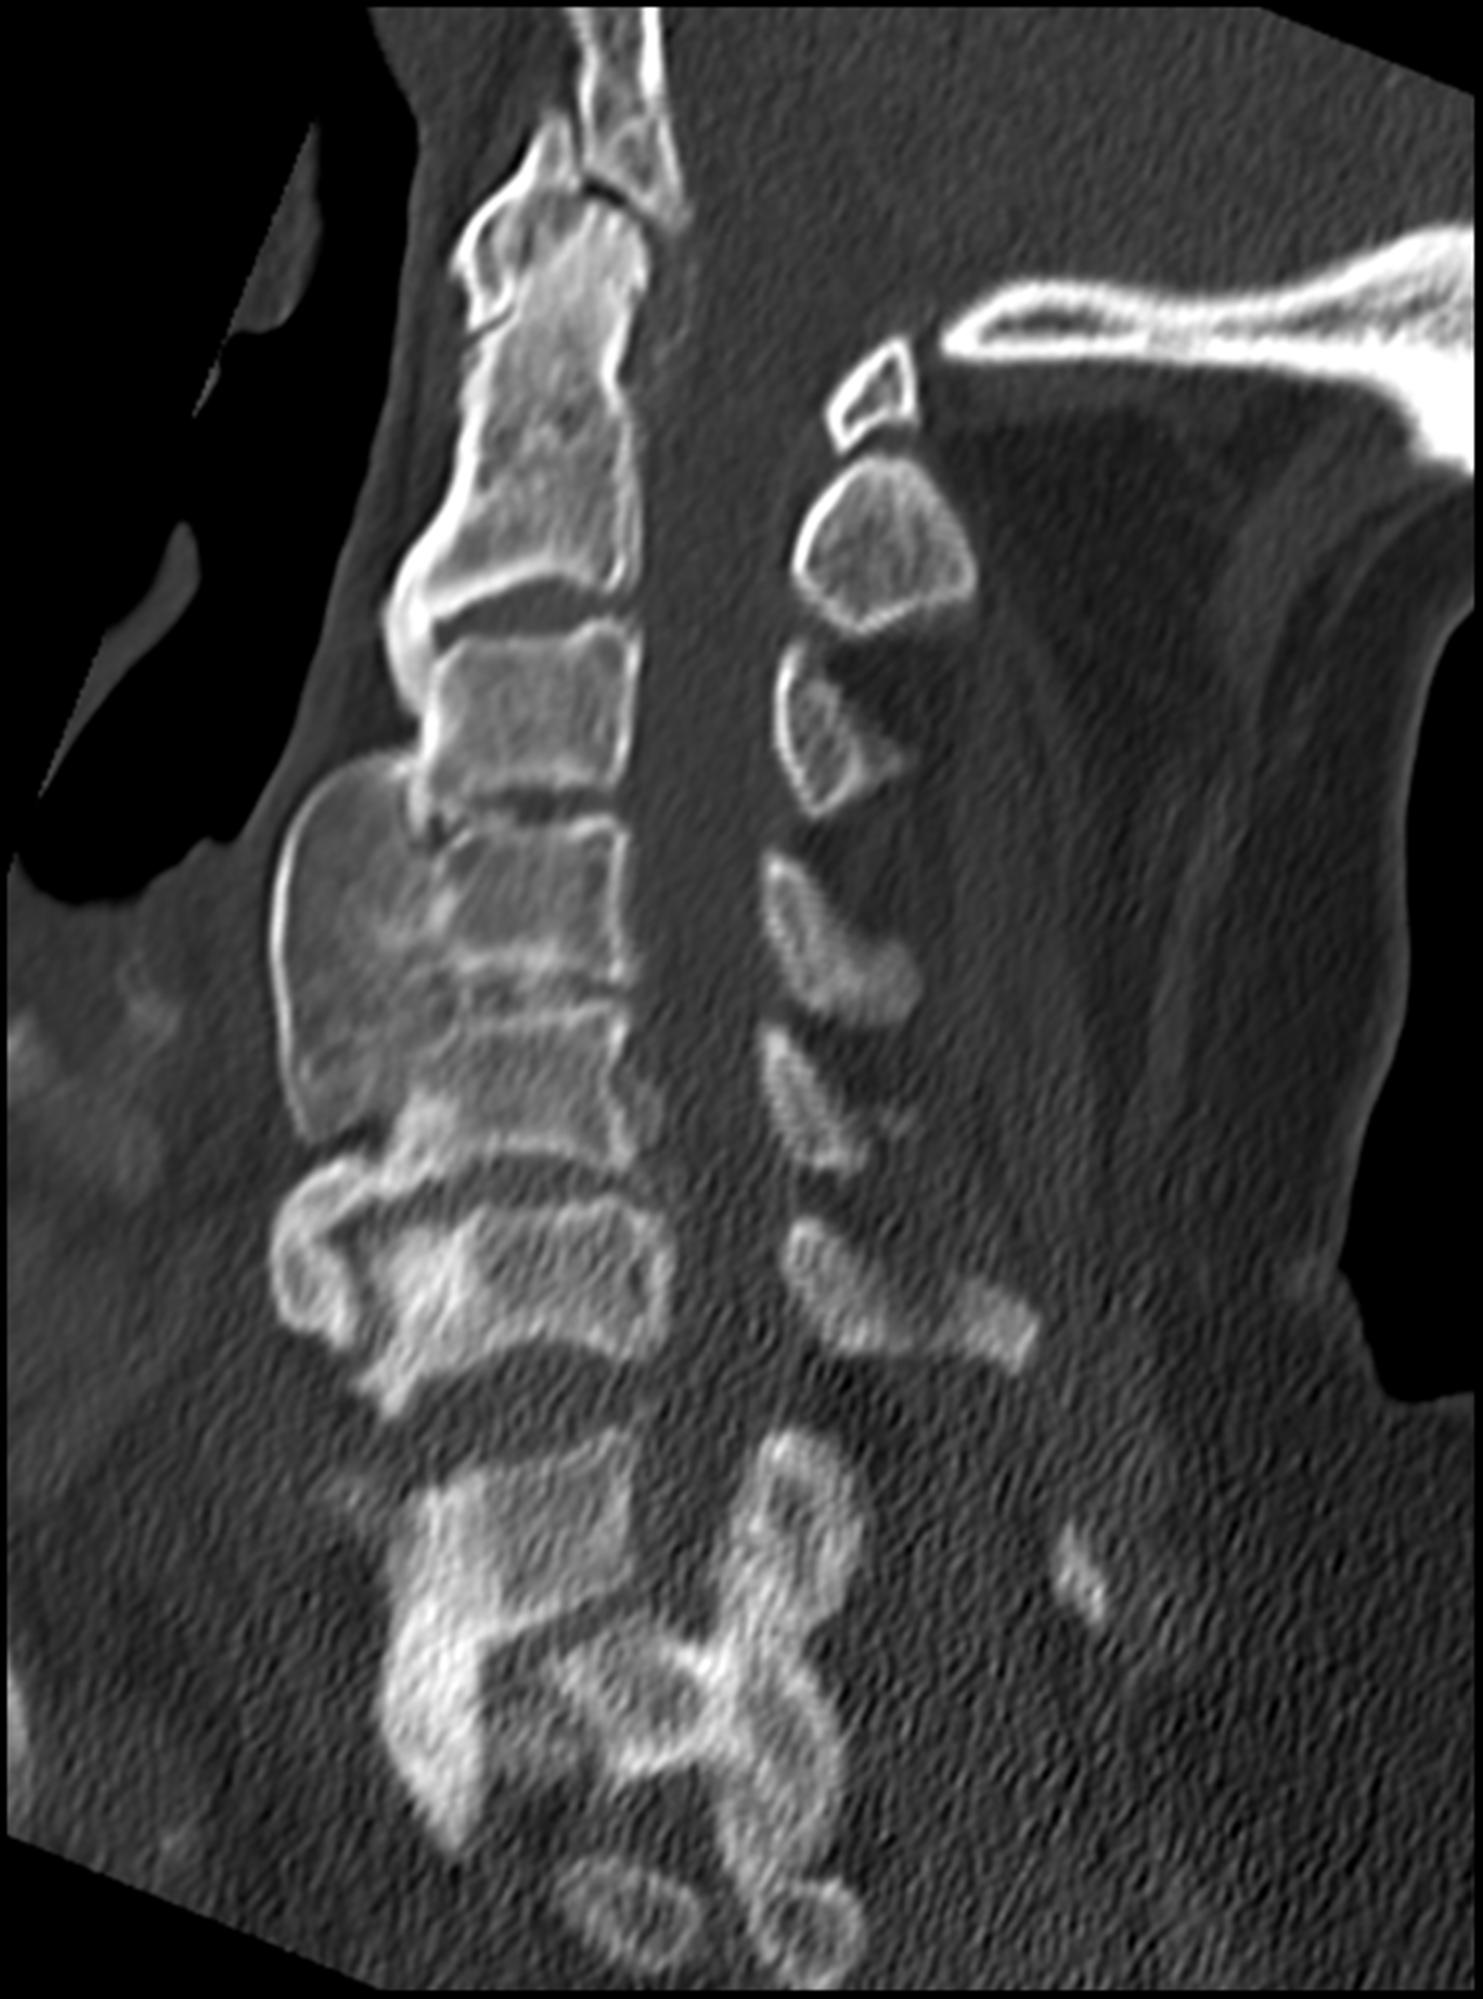

DISH! One of the spinal conditions, but easily detected

DISH (Diffuse Idiopathic Skeletal Hyperostosis) Spine Orthobullets Candle Wax Dish Spine The calcification along the spine has a very unique appearance. Dish, also known as forestier disease, is a common disorder of unknown etiology characterized by enthesopathy of the. The calcification of ligaments, particularly of the anterior longitudinal ligament, has a distinct appearance of candle wax dripping down your. The diagnosis of dish requires the radiological presence of free flowing ossification. Candle Wax Dish Spine.

Image Candle Wax Dish Spine Osteologically, dish primarily affects the spine and in advanced cases, presents with a flowing hyperostosis (with 'dripping. The calcification of ligaments, particularly of the anterior longitudinal ligament, has a distinct appearance of candle wax dripping down your. Some doctors call it cascading or flowing. The calcification along the spine has a very unique appearance. The diagnosis of dish requires the. Candle Wax Dish Spine.

Lateral cervical radiograph showing prominent candle wax osteophytes Candle Wax Dish Spine The calcification of ligaments, particularly of the anterior longitudinal ligament, has a distinct appearance of candle wax dripping down your. Some doctors call it cascading or flowing. The calcification along the spine has a very unique appearance. Dish, also known as forestier disease, is a common disorder of unknown etiology characterized by enthesopathy of the. Osteologically, dish primarily affects the. Candle Wax Dish Spine.

'Flowing candlewax' ossification on thoracic and lumbar spine (T4T5 Candle Wax Dish Spine Osteologically, dish primarily affects the spine and in advanced cases, presents with a flowing hyperostosis (with 'dripping. Some doctors call it cascading or flowing. Dish, also known as forestier disease, is a common disorder of unknown etiology characterized by enthesopathy of the. The diagnosis of dish requires the radiological presence of free flowing ossification (like a flowing candle wax) of. Candle Wax Dish Spine.